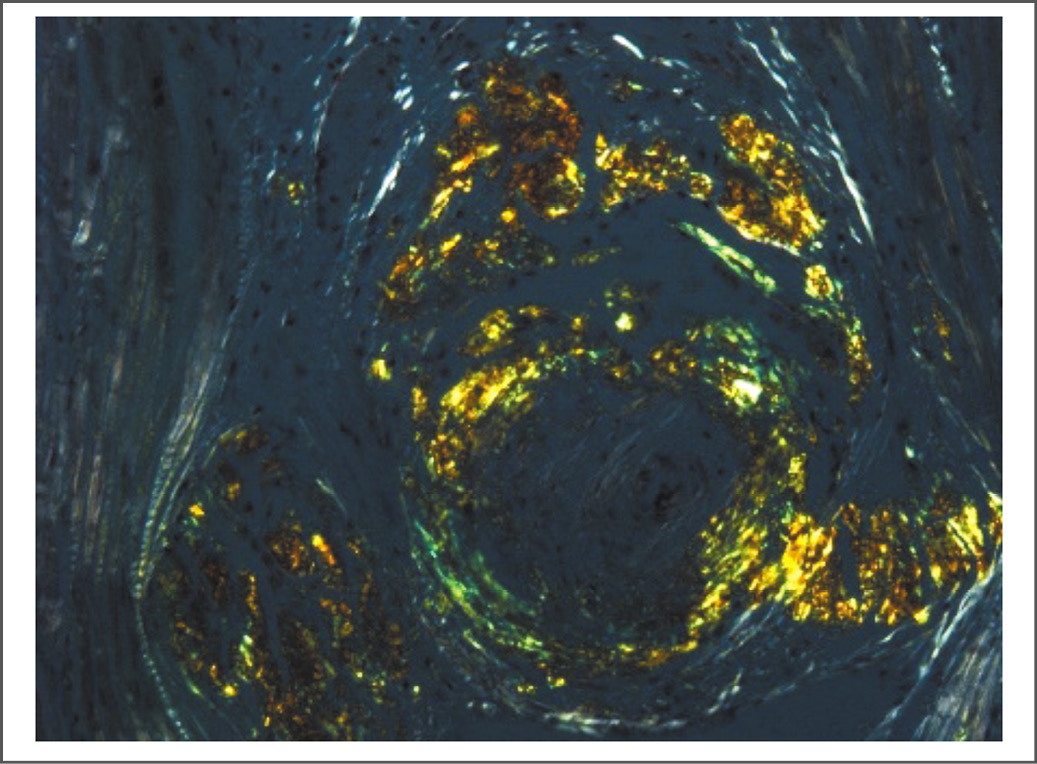

По результатам патологоанатомического исследования постинфарктных очаговых изменений в миокарде не обнаружено, клапаны сердца внешне без особенностей, в коронарных артериях атеросклероз не выражен, стенозов нет. Гистологически верифицирован системный амилоидоз с преимущественным поражением сердца и (в меньшей степени) почек и других органов: в сердце присутствуют отложения амилоида, в основном в стенках сосудов, также они зафиксированы в строме миокарда, клапанах сердца, почках, печени, селезёнке, лёгких, поджелудочной, щитовидной и паращитовидных железах (рис. 4, 5). Толщина стенки ЛЖ – 10–12 мм, толщина МЖП – 10 мм, толщина стенки правого желудочка – 2 мм, масса сердца – 360 г. Для установления типа амилоида выполнено иммуногистохимическое исследование с применением антисывороток к основным типам амилоидного белка. На основании результатов исследования установлен диагноз AL-κ-амилоидоза.

Рис. 4. Периваскулярное отложение амилоида по результатам гистологического исследования. Ув. 100. Окраска Конго красным.

Fig. 4. Perivascular amyloid deposition based on histological studies. Magnification 100. Congo red.

Рис. 5. Периваскулярное отложение амилоида по результатам гистологического исследования. Ув. 20. Окраска Конго красным. Микроскопия в поляризованном свете. Миокард.

Fig. 5. Perivascular amyloid deposition based on histological studies. Magnification 20. Congo coloration red. Microscopy in polarized light. Myocardium.

Оценивая ретроспективно описанный клинический случай, мы пришли к следующим выводам. Кардиальный амилоидоз, протекающий с преимущественным периваскулярным отложением амилоида, может симулировать ишемическую болезнь сердца, в том числе ИМ, и не сопровождаться утолщением стенок миокарда с возникновением рестриктивной кардиомиопатии. Развивающаяся в этом случае сердечная недостаточность, по-видимому, обусловлена выраженными микроваскулярными нарушениями, присутствие которых доказано при данной патологии [3, 8].